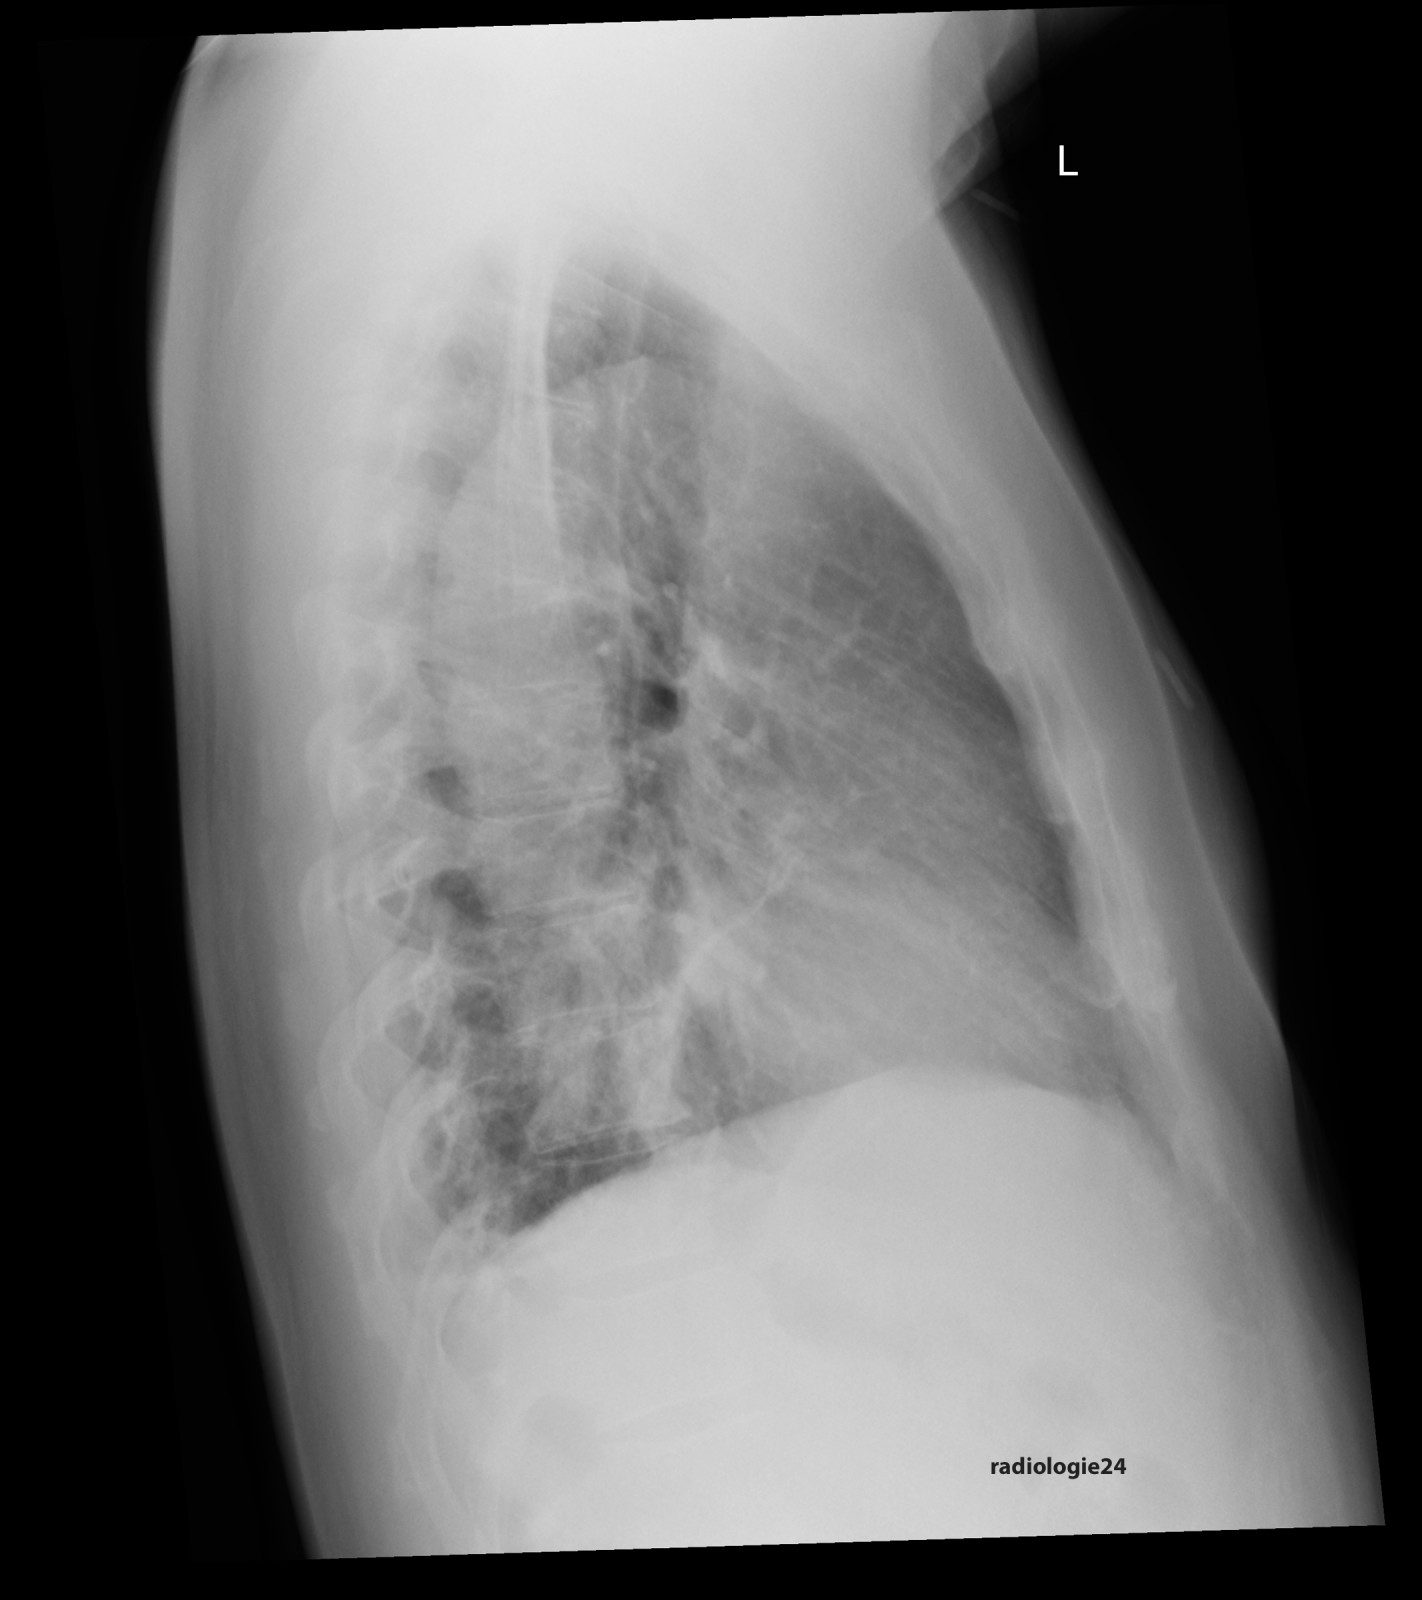

Röntgenfall des Monats Oktober 2017 mit Auflösung

48 jähriger Patient. Klinische Angaben: Thoraxschmerzen, afebril, hypertensiv entgleist. Fragestellung: Infektzeichen? Kardiale Kompensation? Diagnose? Weitere radiologische Diagnostik?